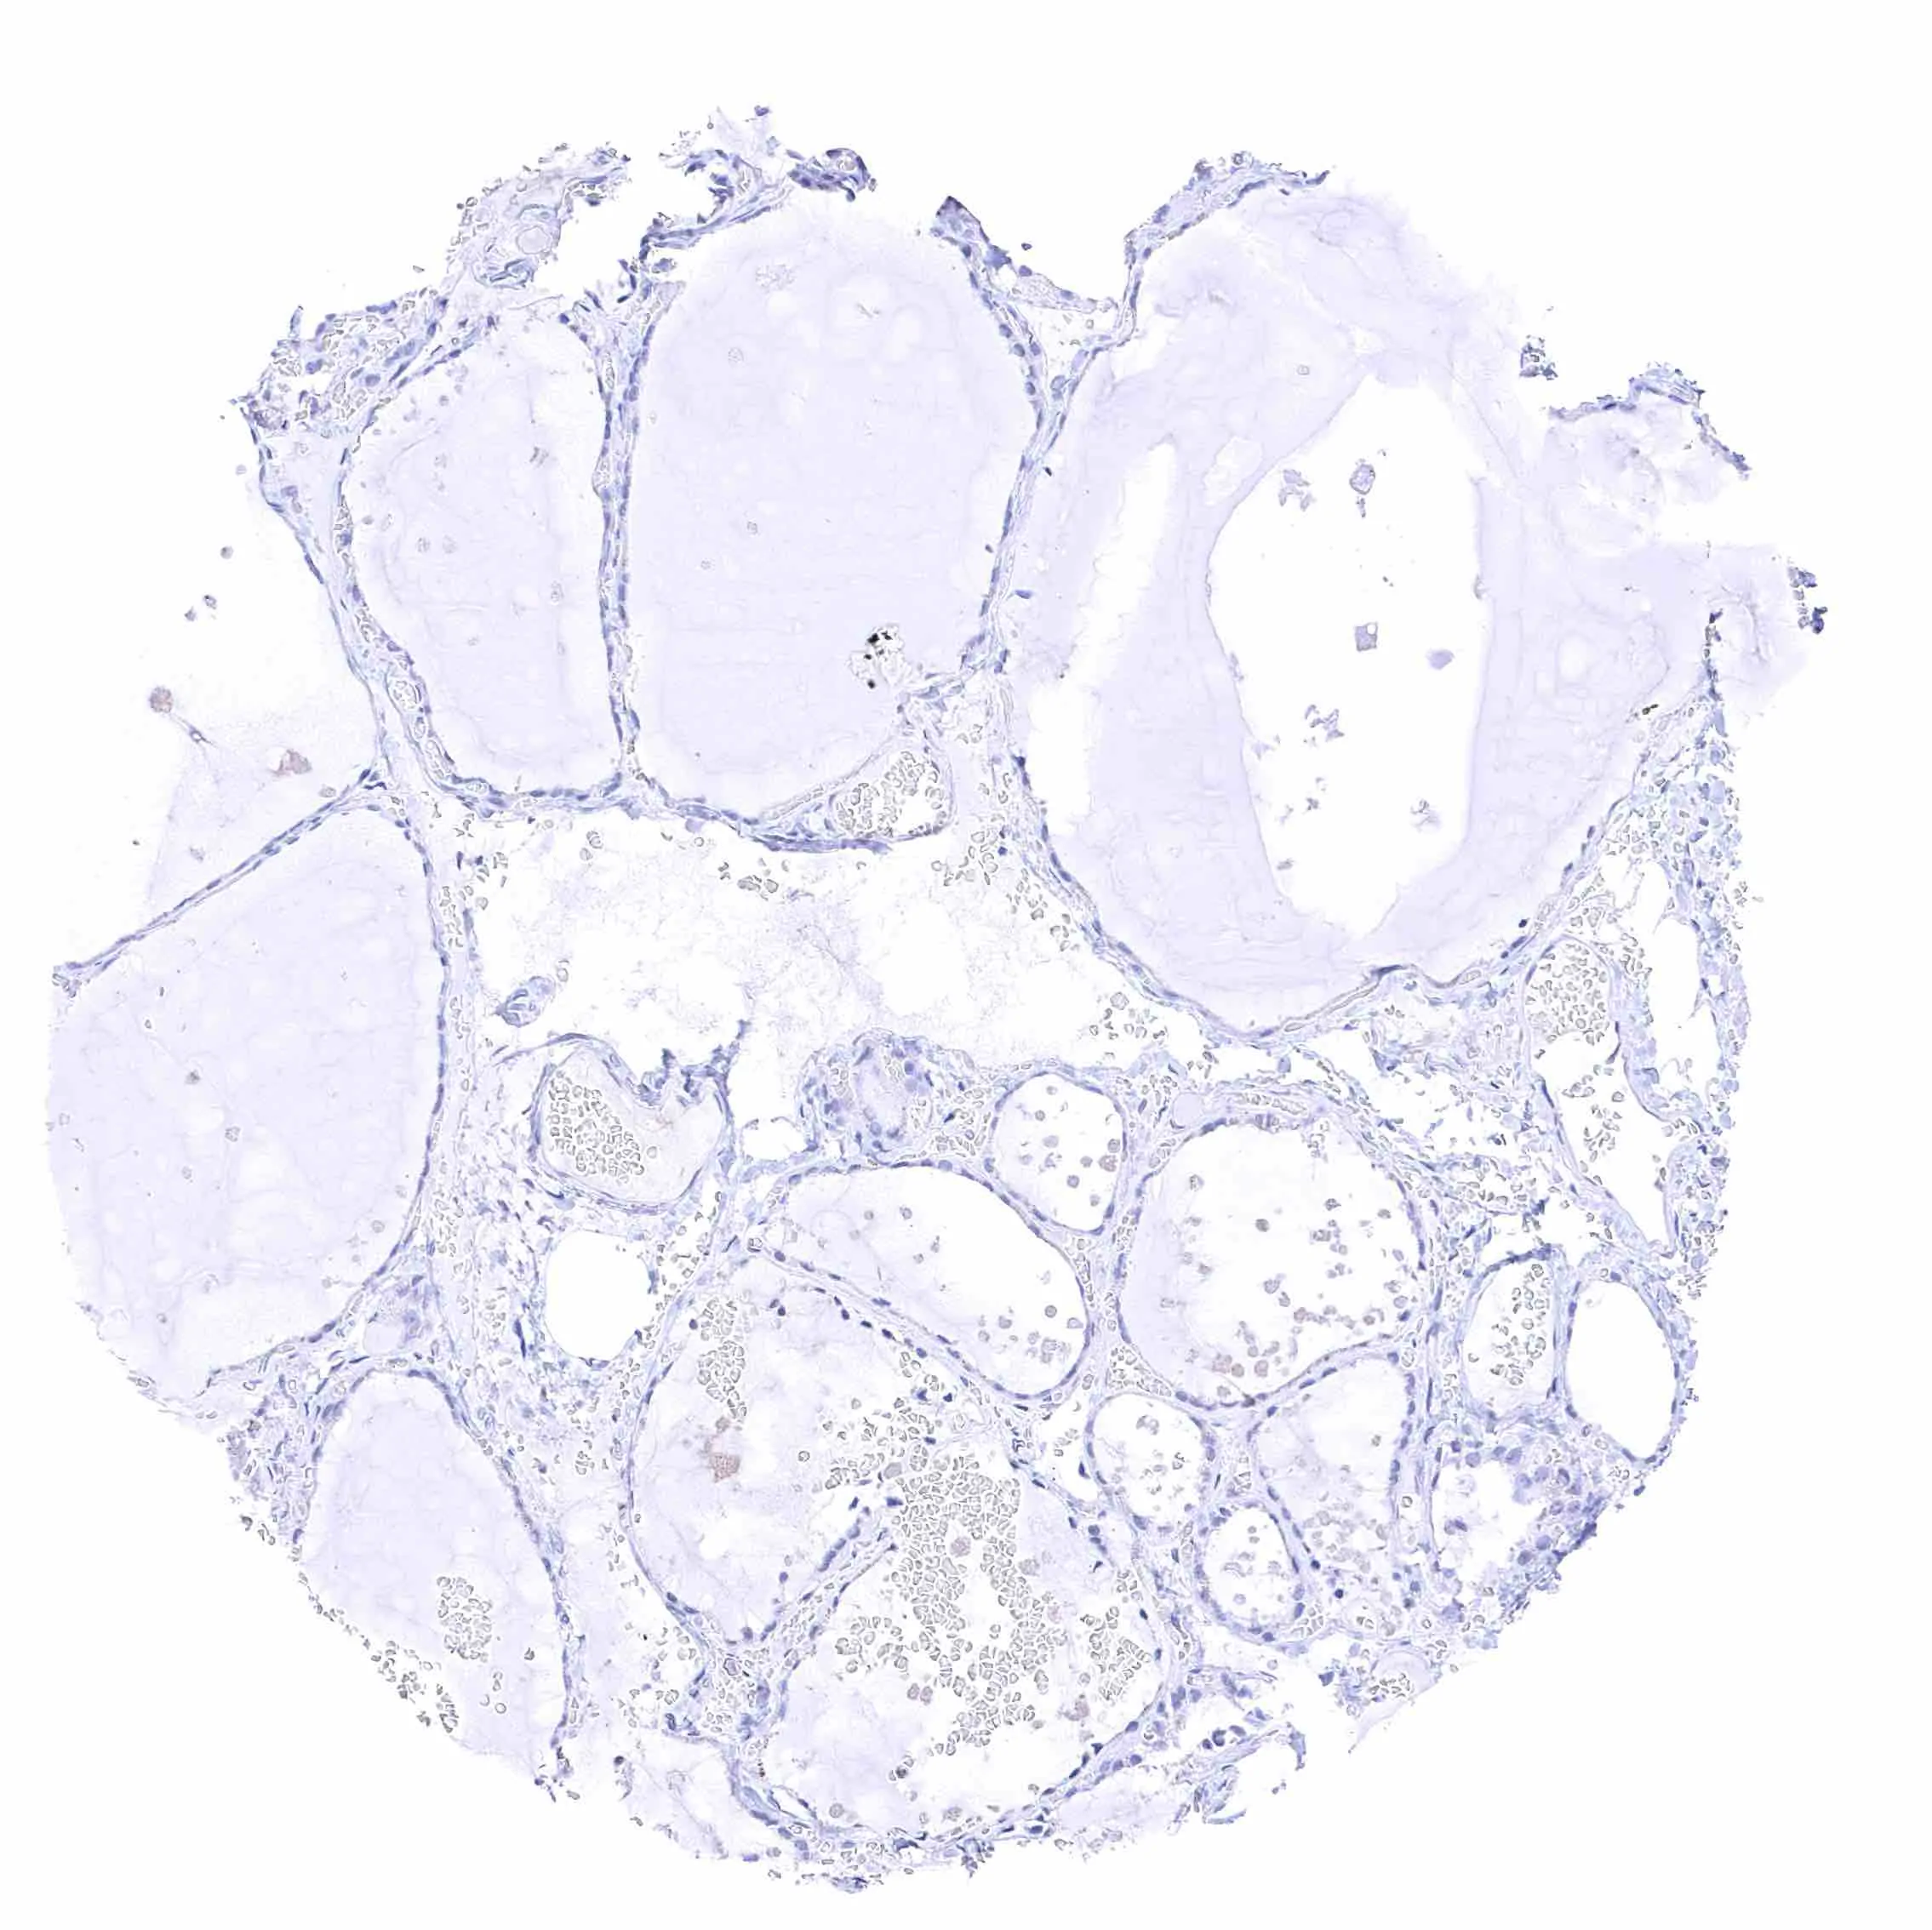

Thyroid gland